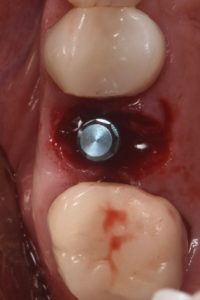

This video demonstrates a fully guided immediate implant placement protocol following premolar extraction, combined with immediate provisional restoration. The case highlights a digitally driven workflow designed to enhance accuracy, efficiency, and prosthetically guided implant positioning.

Step-by-step, the procedure covers atraumatic tooth extraction, guided implant placement using a surgical guide, and chairside fabrication and delivery of an immediate provisional restoration. Clinical considerations for achieving primary stability, soft tissue preservation, and optimal emergence profile are emphasized to support predictable esthetic and functional outcomes.